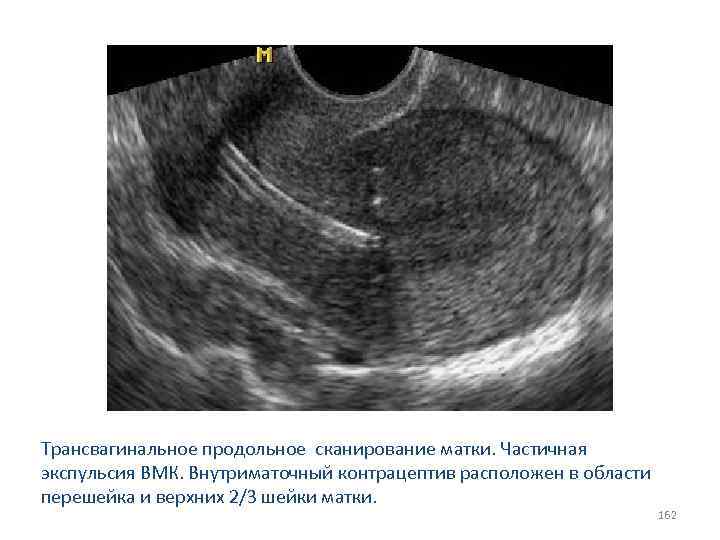

Трансвагинальное продольное сканирование матки. Частичная экспульсия ВМК. Внутриматочный контрацептив расположен в области перешейка и верхних 2/3 шейки матки. 162